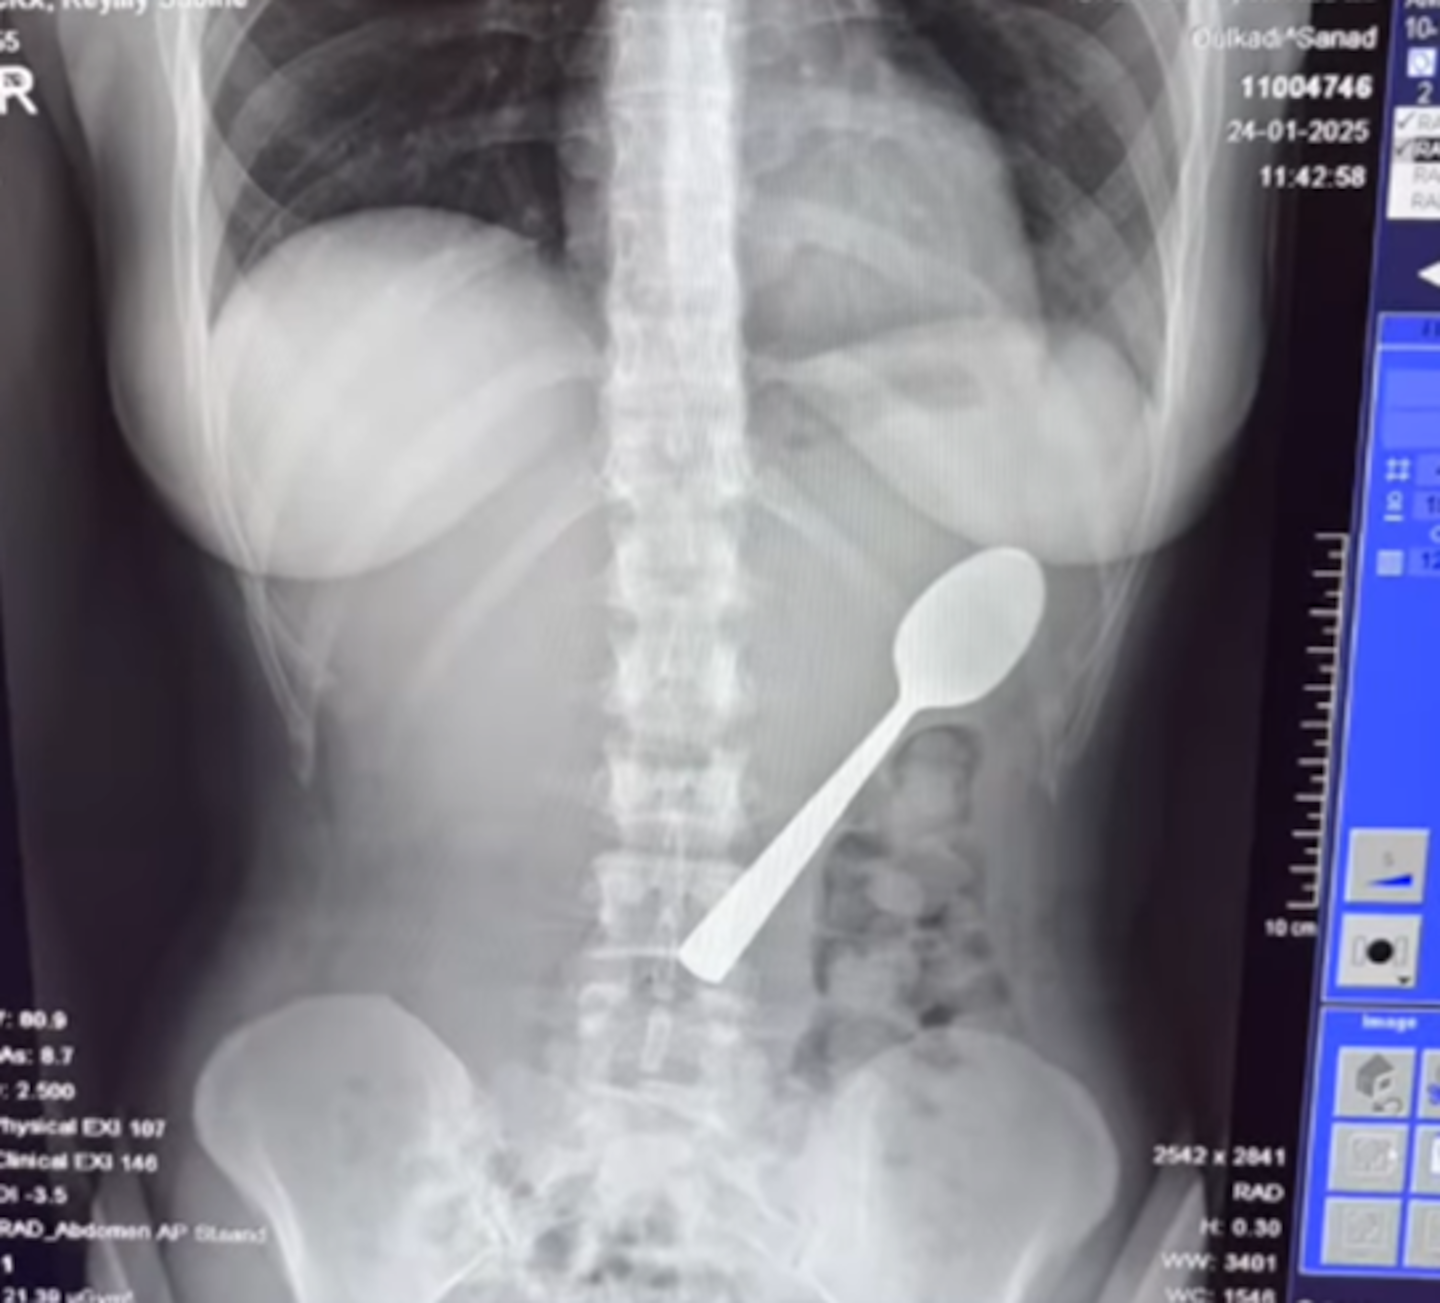

A woman was left in a panic after she swallowed a 17cm spoon when her dog jumped on her as she was eating yoghurt.

“There was a 17cm spoon in my stomach.

Doctors advised her the spoon was too big to pass naturally, and that she would have to wait at home until an appointment could be scheduled for a gastroscopy, Metro reported.

Two days later, Amelinckx underwent minor surgery.